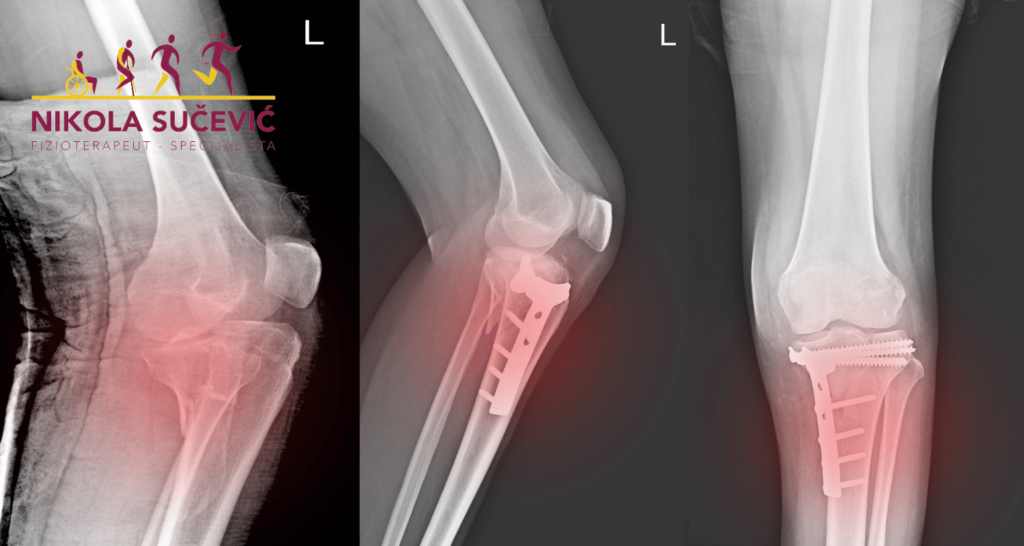

Prelom tibije

Fraktura tibije – Pregled Fraktura tibijalnog platoa odnosi se na prelom ili pukotinu na vrhu kosti potkolenice, u kolenu. Uključuje površinu hrskavice kolenog zgloba. Uzroci i simptomi preloma potkolenice Potkolenica je ključna koštana struktura koja podržava telesnu težinu prilikom trčanja, hodanja ili skakanja. Do preloma platoa tibije občno dolazi usled visokoenergetskog udara. Ovakva vrste povrede […]